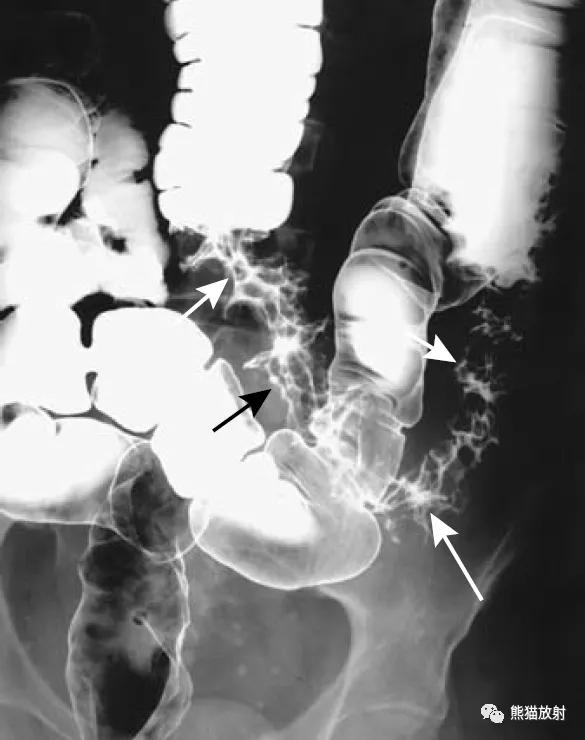

同一患者:结肠肝曲腺癌(黑箭)、升结肠腺瘤(白箭头)

升结肠癌(箭)和横结肠浸润性腺癌(箭头)。